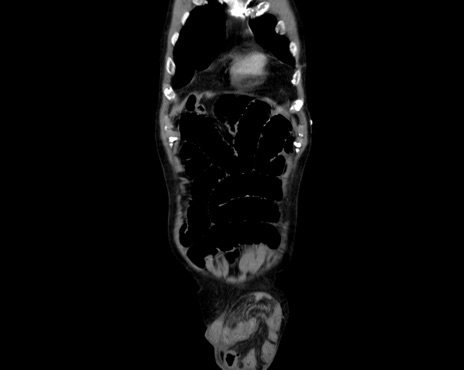

症例26(冠状断像)

【症例】80歳代男性

【主訴】嘔吐

【現病歴】昨晩2回嘔吐あり、今朝になっても嘔吐あり。来院。

【既往歴】胃潰瘍

【身体所見】意識清明、BT 37.6℃、BP 166/95mmHg、HR 100bpm、SpO2 97%、腹部:平坦・軟、腸蠕動音聴取良好、圧痛なし。

【データ】WBC 21900、CRP 1.4